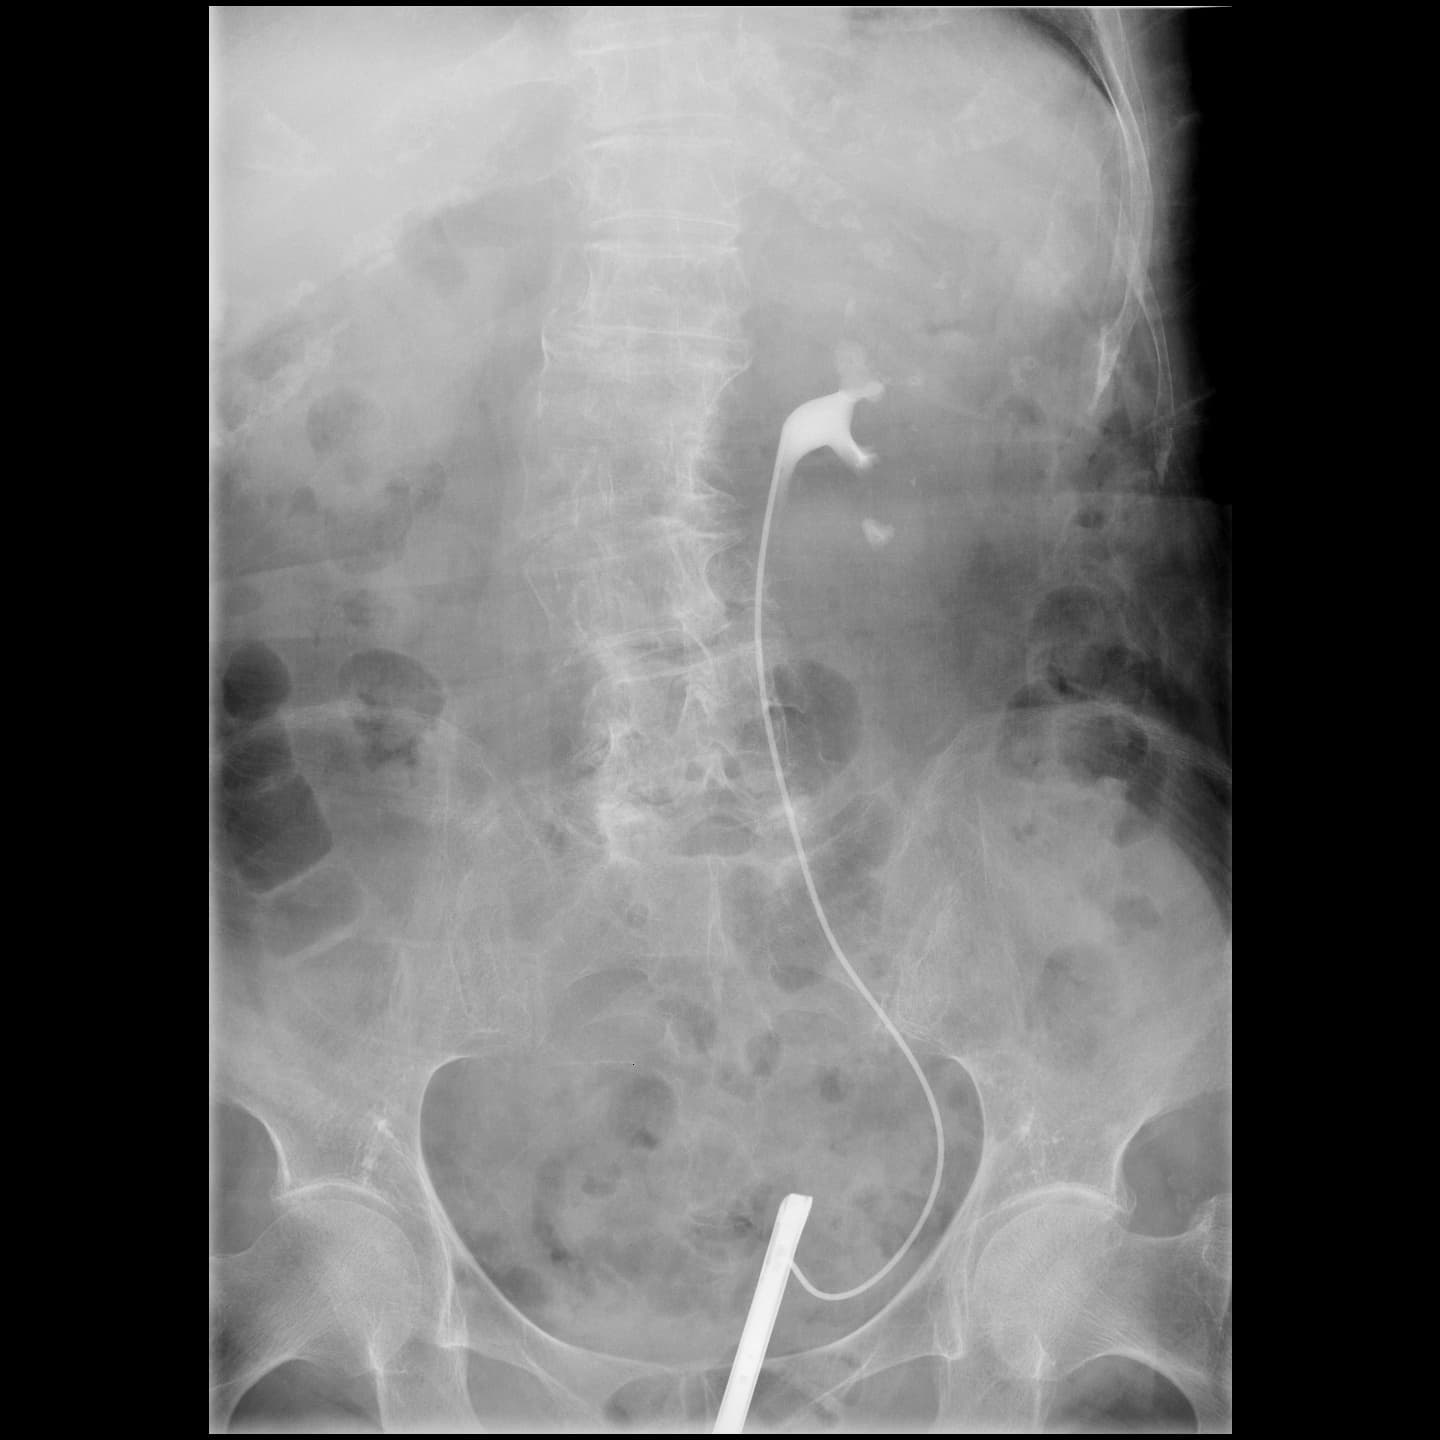

泌尿器部門に特化した装置です。腎臓や尿路、膀胱の機能や形態を調べるため、尿路造影検査を行っています。

主な検査として、X線透視下で尿管カテーテルの挿入を行っています。

尿管皮膚婁、腎瘻・膀胱瘻増設などの治療も行います。

また、小児に起こりやすい膀胱尿管逆流症に対して、排尿時膀胱尿道撮影なども行っています。